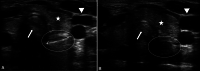

Purpose: Foreign body (FB) ingestions represent a common problem in children. History and physical examination are commonly not enough to diagnose a foreign body ingestion; therefore, conventional radiography is routinely used to detect them. Point-of-care ultrasound is widely used in the emergency department for several diagnostic applications but there are few articles describing the possibility to use point-of-care ultrasound to detect ingested foreign bodies, and the necessary training to get competent in this application. The main objective of this paper is to illustrate the use of point-of-care ultrasound (POCUS) to detect ingested foreign bodies. The secondary objective is to describe a limited training, necessary for emergency pediatricians, to obtain this skill.

Methods: This is a case series of eight pediatric patients who presented to the pediatric Emergency Department (ED), with suspected ingestion of FB, and were assessed with POCUS. Physician sonographers were two pediatricians and three residents in pediatrics working in two Italian Pediatric EDs. All sonographers participated in a 2-day POCUS workshop which included the most common pediatric POCUS applications.

Results: POCUS, performed by emergency pediatricians who participated to a limited training, allowed to always identify the foreign bodies ingested.

Conclusions: We demonstrate that an appropriate and limited training allows pediatric emergency physicians to correctly identify foreign body in the esophagus or stomach. Point-of-care ultrasound in foreign body ingestion in the Emergency Department may allow to prioritize the escalation of care in children and it can contribute to reduce the time to endoscopic management when needed.